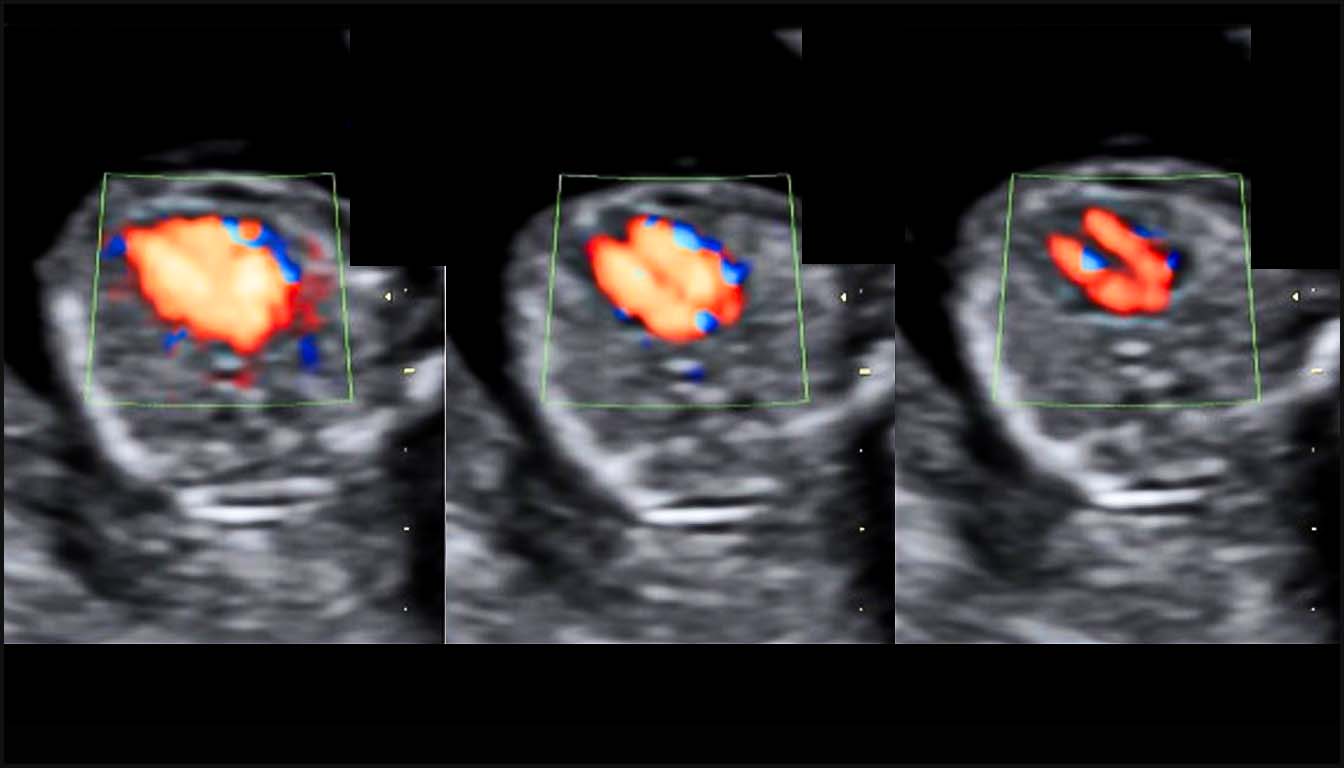

• La coupe des quatre cavités (4C) : Le Doppler couleur permet de visualiser deux flux d’entrée ventriculaires distincts, laminaires et de taille similaire. Il aide à diagnostiquer immédiatement des anomalies comme l’atrésie tricuspide (absence de flux à droite) ou les canaux atrioventriculaires (CAV), souvent identifiables par un flux unique en forme de “Y”.

• Pattern AVSD : Un flux d’entrée unique en forme de « Y » remplit les deux ventricules simultanément, traduisant la présence d’une valve AV commune.

4. Canal Atrioventriculaire (CAV) : Valve unique commune (image en “Y” au Doppler), défaut des septums auriculaire et ventriculaire, et perte de l’offset normal des valves.

4. Canal atrioventriculaire (CAV) : Typiquement associé à la trisomie 21, il présente une valve unique commune, un défaut septal central et un flux Doppler d’entrée ventriculaire en forme de “Y”.